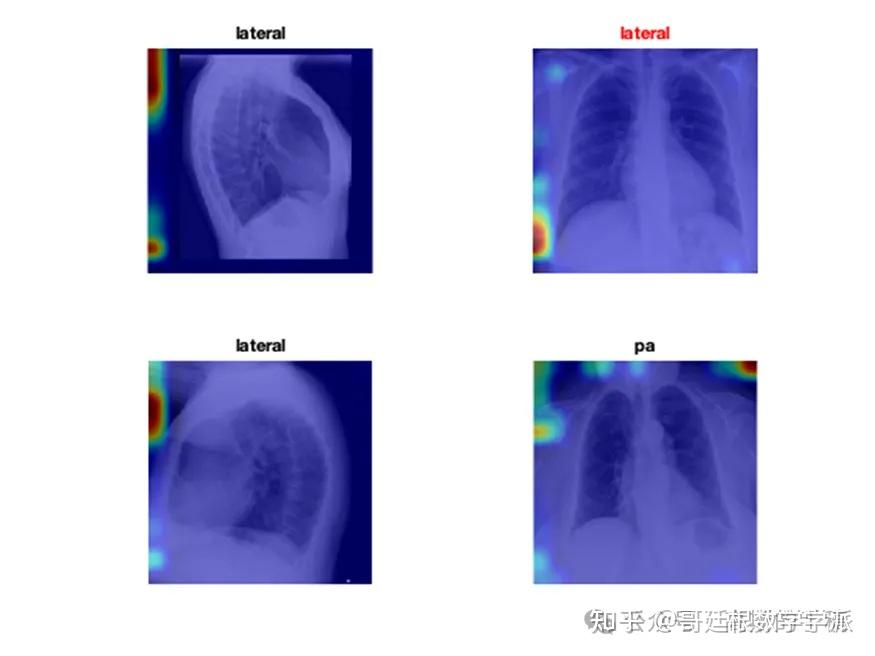

医学图像的深度学习可解释性(MATLAB R2021B)